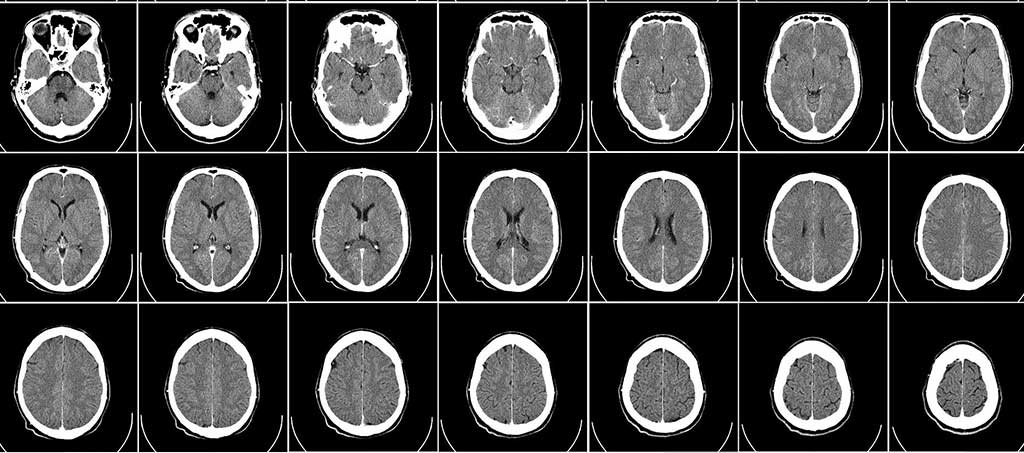

Traumatism cranian

Traumatism cranian – cauze, simptome, tratament si dieta recomandata